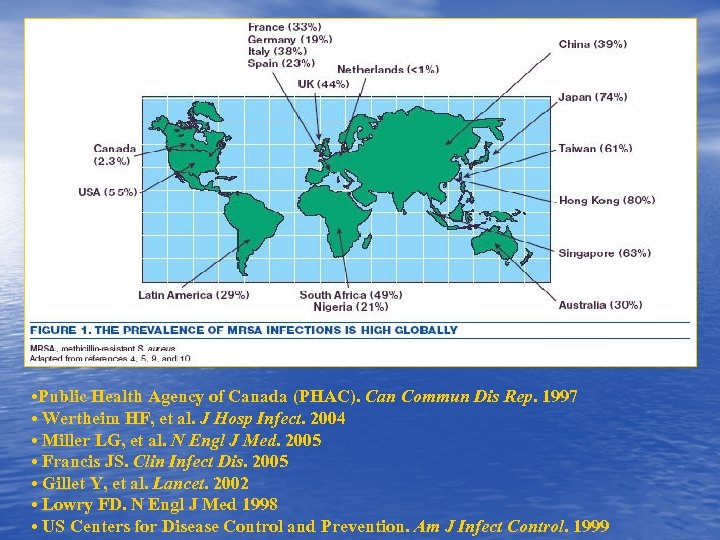

• Public Health Agency of Canada (PHAC). Can Commun Dis Rep. 1997 • Wertheim HF, et al. J Hosp Infect. 2004 • Miller LG, et al. N Engl J Med. 2005 • Francis JS. Clin Infect Dis. 2005 • Gillet Y, et al. Lancet. 2002 • Lowry FD. N Engl J Med 1998 • US Centers for Disease Control and Prevention. Am J Infect Control. 1999

• Public Health Agency of Canada (PHAC). Can Commun Dis Rep. 1997 • Wertheim HF, et al. J Hosp Infect. 2004 • Miller LG, et al. N Engl J Med. 2005 • Francis JS. Clin Infect Dis. 2005 • Gillet Y, et al. Lancet. 2002 • Lowry FD. N Engl J Med 1998 • US Centers for Disease Control and Prevention. Am J Infect Control. 1999